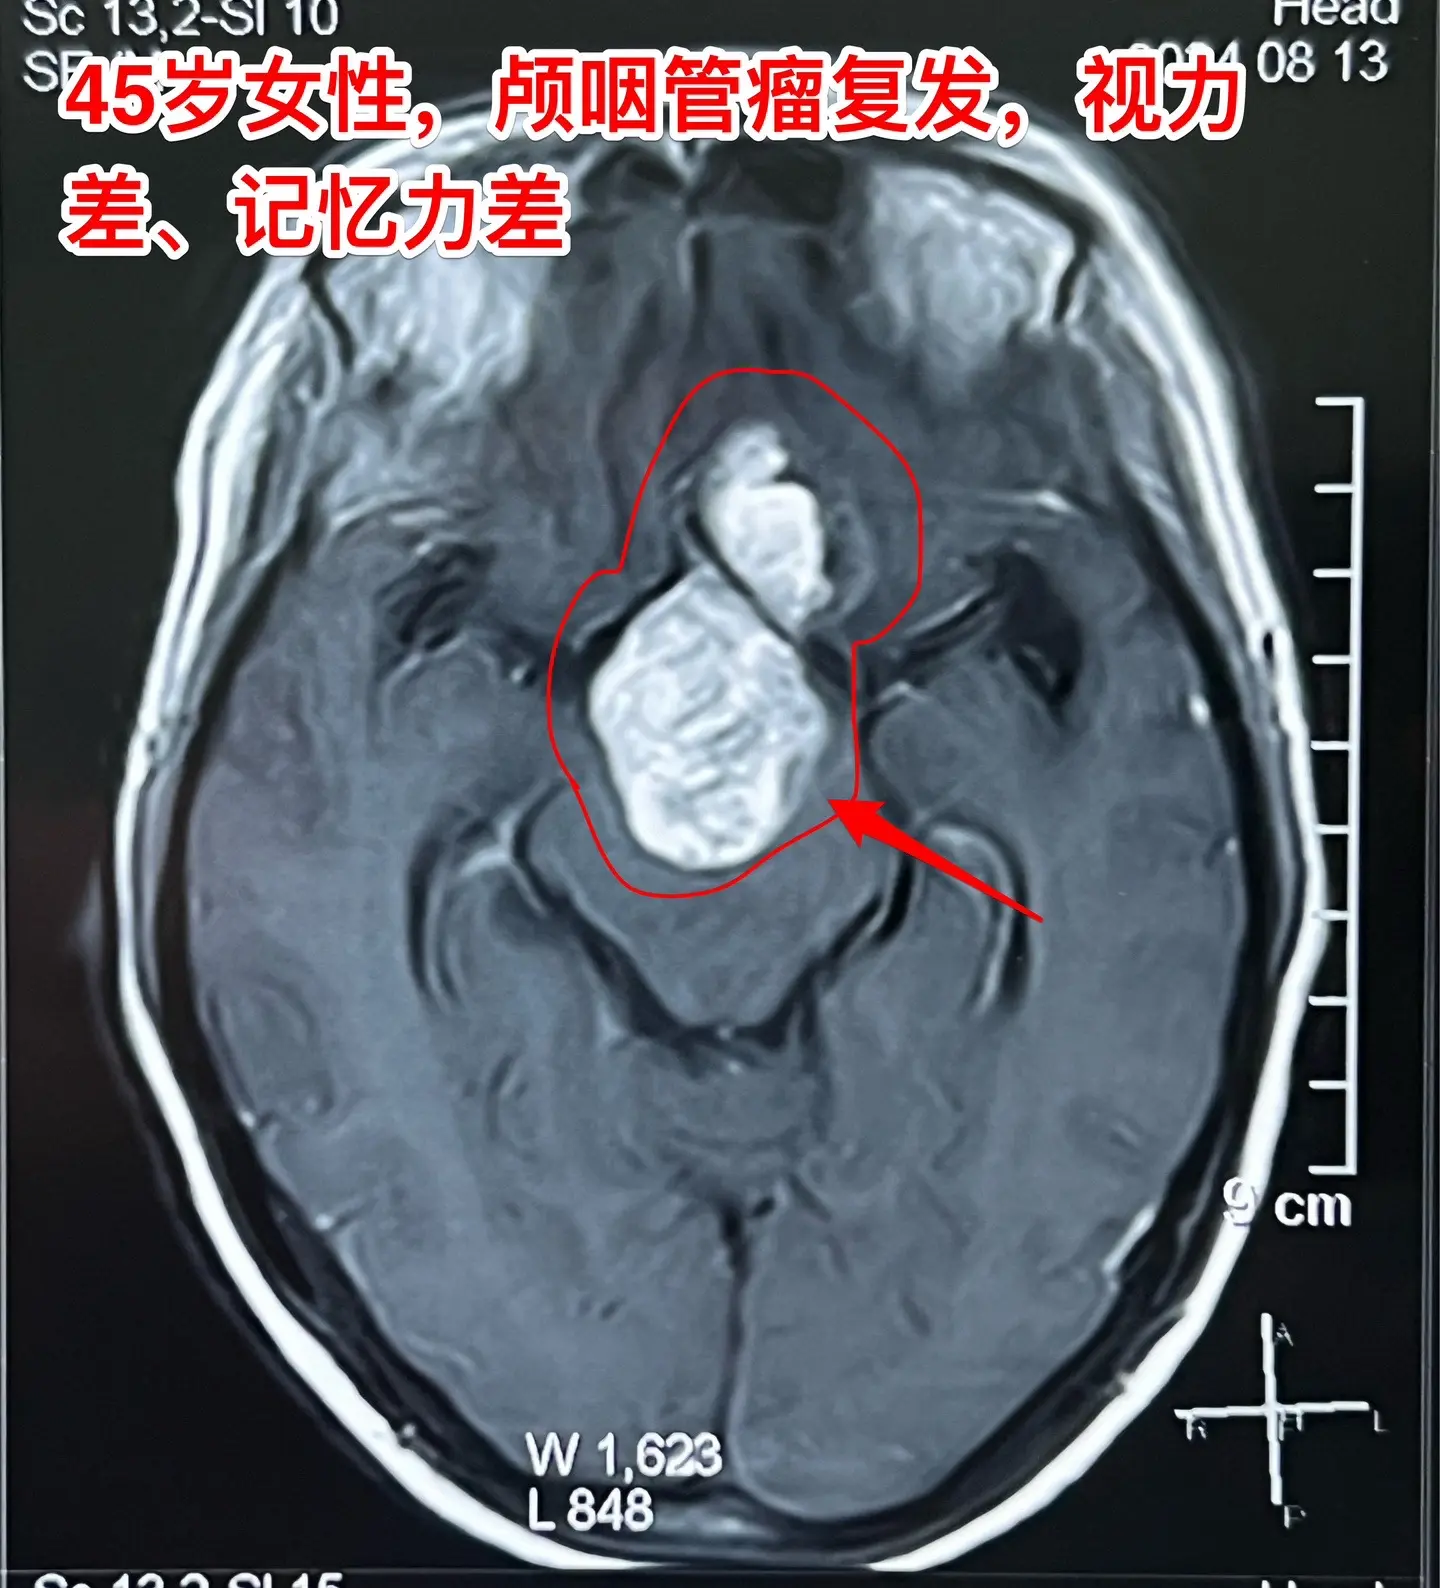

巨大的颅咽管瘤。45岁浙江女性,在外院作了颅咽管瘤手术不到一年,作磁共振显示肿瘤复发,而且体积巨大。 病人视力很差,记忆力也差,精神不好。 这么大的颅咽管瘤一般是需要作手术的。显而易见是这样的手术是很有难度的,很考验医生的技术和能力! 从影像学资料可以看出,这是乳头型颅咽管瘤。如果害怕作手术,对于运气好、经济状况好的病人,也可以试一试靶向药,也许有效。 这个病人选择了作手术!8月16日我们经过九个小时的紧张奋战,将肿瘤完全切除了。手术后CT结果很好。